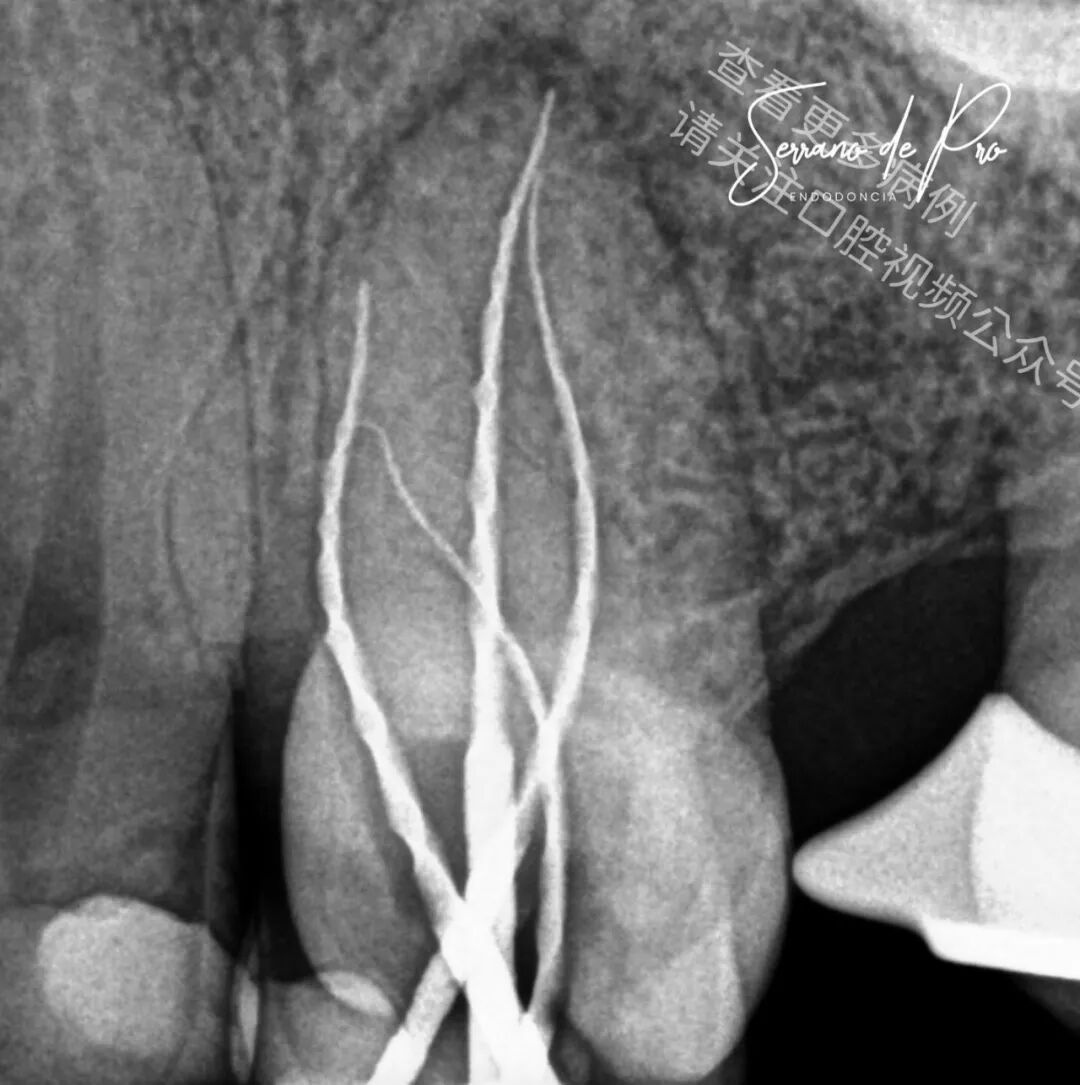

这是一个非常奇特的病例,24号牙和25号牙并非处于它们的正常位置,而是并排生长,拍出的X光片十分惊人。能如此清晰地看到根管充填的细节可不是每天都有的事。25号牙牙髓坏死,24号牙则患有严重的牙髓炎。

两颗牙都使用了来自FKG Iberia公司的Raceevo锉预备到30.04的锥度,并用Avalon Biomed公司的Neosealer Flo封闭剂以及Zarc4endo公司的产品配合WaveOne垂直加压(WVC)技术进行根管充填。